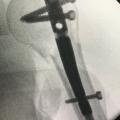

• l’ostéosynthèse consistant en une réduc­tion directe ou indirecte de la fracture, puis en son immobilisation par du matériel intra-osseux (broche, clous, vis, plaques), ou parfois à l’extérieur du membre (fixateur externe), notamment en cas de fracture ouverte grave (fig. 2). Une immobilisation complémentaire par attelle ou plâtre peut être associée.

L’évolution normale d’une fracture conduit à sa consolidation et au rétablissement de la fonction du membre. Cette évolution peut être compliquée par un déplacement secondaire, un retard de consolidation, une non-consoli­dation (pseudarthrose) ou une consolidation non anatomique (cal vicieux) [fig. 3], pouvant nécessiter des chirurgies complémentaires.

Les causes sont variables : hématome, ­lésion des parties molles, infection débutante, démontage de l’ostéosynthèse, ­luxation ou fracture périprothétique (fig. 4). Un avis chirurgical urgent doit être sollicité, parfois précédé d’un bilan d’imagerie radiologique simple et d’un ­bilan biologique (hémogramme, protéine C réactive [CRP]).